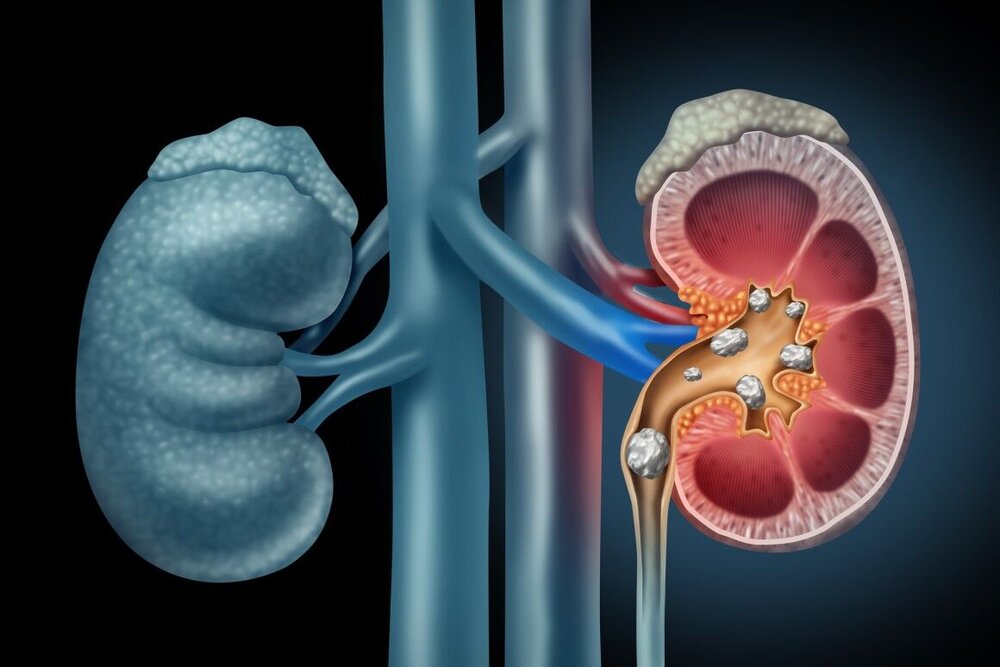

سنگ کلیه: نوشیدن آب شنبلیله که به مدت یک ماه با معده خالی در صبح خیس خورده است به حل سریع سنگ ها کمک می کند و سلامت کلیه ها و مجاری ادراری را حفظ می کند.